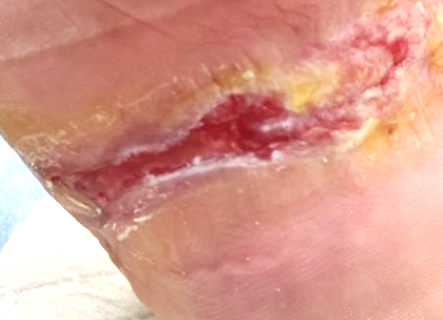

• lesione da decubito plantare presente da 15 anni

• lesione da decubito plantare a 20 gg post 3 sedute di Fluorescent Light Energy